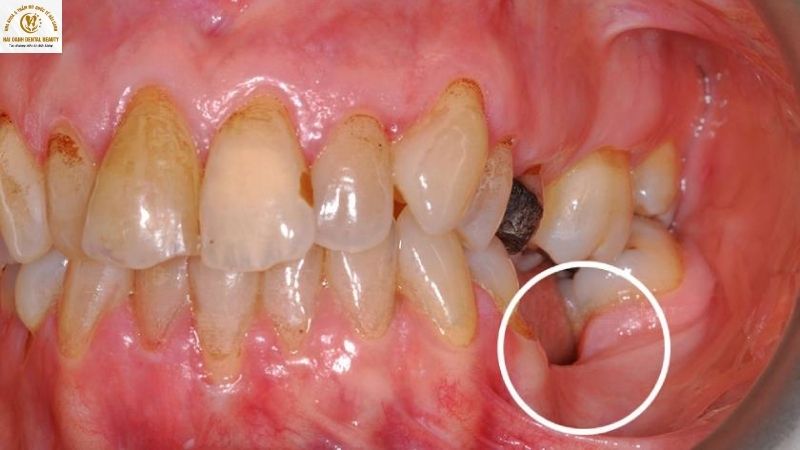

2.1. Tụt lợi và vùng mất răng bị lõm xuống

Đây là một trong những dấu hiệu sớm và rõ ràng nhất của tiêu xương. Khi không còn chân răng để nâng đỡ, xương ổ răng sẽ dần teo lại. Phần nướu bao phủ lên xương cũng sẽ theo đó mà tụt xuống, khiến vùng mất răng trông lõm vào và sâu hơn so với các vùng lân cận. Tình trạng này không chỉ gây mất thẩm mỹ mà còn tạo ra các khe hở, dễ tích tụ thức ăn và vi khuẩn.

2.3. Răng xô lệch và trồi dài

Khi xương hàm bị tiêu biến, các răng còn lại sẽ mất đi nền móng vững chắc. Các răng này có xu hướng xô lệch, nghiêng đổ vào khoảng trống của chiếc răng đã mất. Đồng thời, răng đối diện trên cung hàm cũng có xu hướng trồi dài ra để tìm kiếm khớp cắn. Điều này dẫn đến sự mất cân bằng khớp cắn, gây khó khăn khi ăn nhai, đau khớp thái dương hàm cũng như làm tăng nguy cơ mất thêm nhiều răng khác.